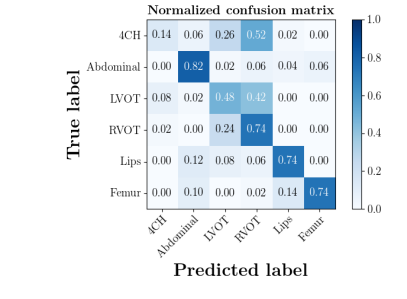

The confusion matrices in Fig. 8(b) show the effectiveness of unlabeled data in the proposed method. The classification accuracy of Femur and Lips in MIDNet improves when using unlabeled data.

| With unlabeled data | Without unlabeled data |

|

|